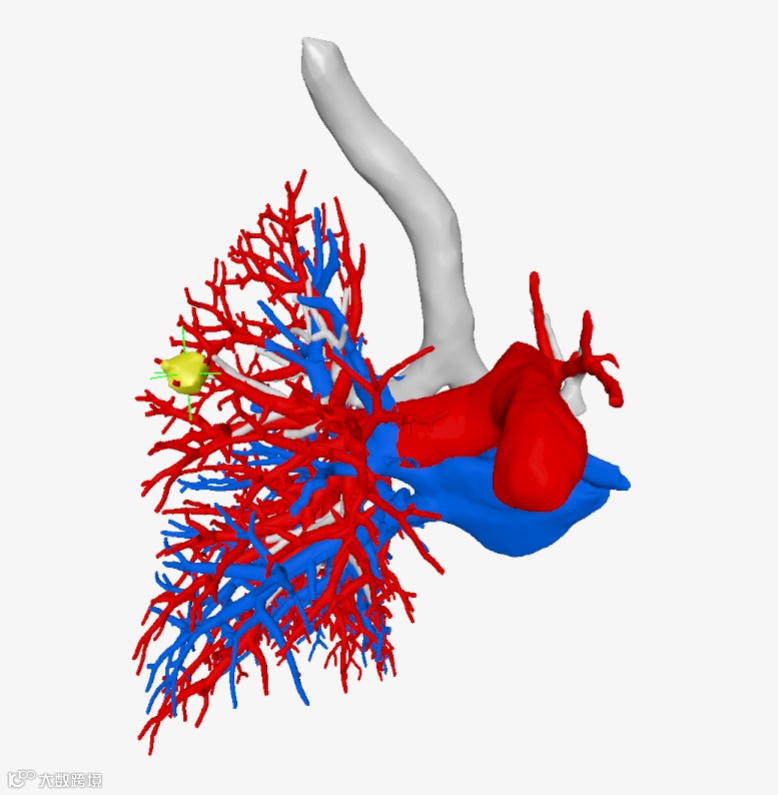

▲▲▲三维重建血管

该院胸外科手术团队用瀚依科技的AI三维重建服务,真实还原了结节的大小、位置和深度,全方位、多维度地观察了患者结节的空间位置、结节与周遭脏器粘连程度、结节对血管的侵占情况,并对手术需要的重要信息进行精准定量分析。

智能识别术后缺失的左肺肺段 -

对发生形态学代偿的右肺肺段进行精确分割 -

对右肺上叶前段实性结节的准确定位